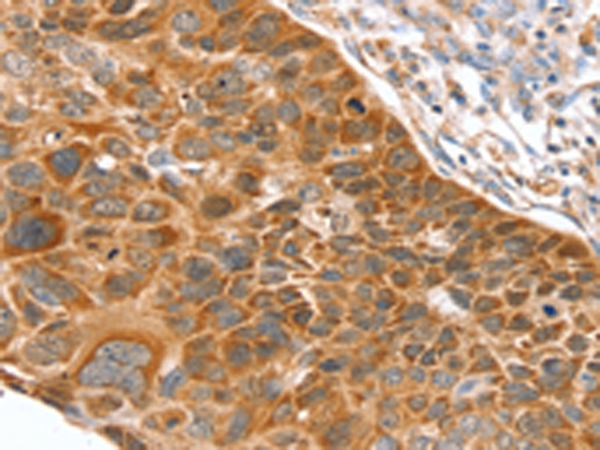

分类: 科研抗体货号: P08761别名: EPIPIN; SERPIN11应用: WB,IHC反应种属: Human, Mouse